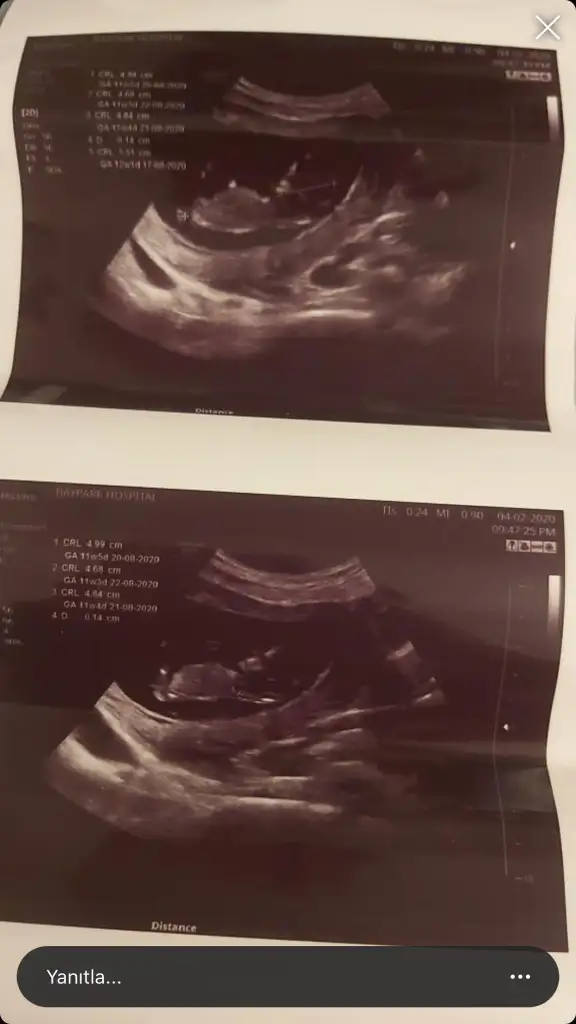

Emin olmamakla birlikte sanki kız nub tarafı çok karanlık başka usg varmı paylaşınEki Görüntüle 2590346 Eki Görüntüle 2590346 Çok belirgin değil ama 12.hafta usg mizIkra meyra Eki Görüntüle 2590346

10+4 te ki vardı ona da kız demiştinizEmin olmamakla birlikte sanki kız nub tarafı çok karanlık başka usg varmı paylaşın